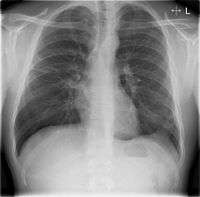

Chest X-rays and X-ray computed tomography (CT) can reveal areas of opacity (seen as white), indicating consolidation. CAP does not always appear on x-rays, because the disease is in its initial stages or involves a part of the lung an x-ray does not see well. In some cases, chest CT can reveal pneumonia not seen on x-rays. X-rays can often mislead, as Heart failure or other types of lung damage can mimic CAP on x-rays.[12]

Chest X-rays of a CAP patient before (left) and after treatment